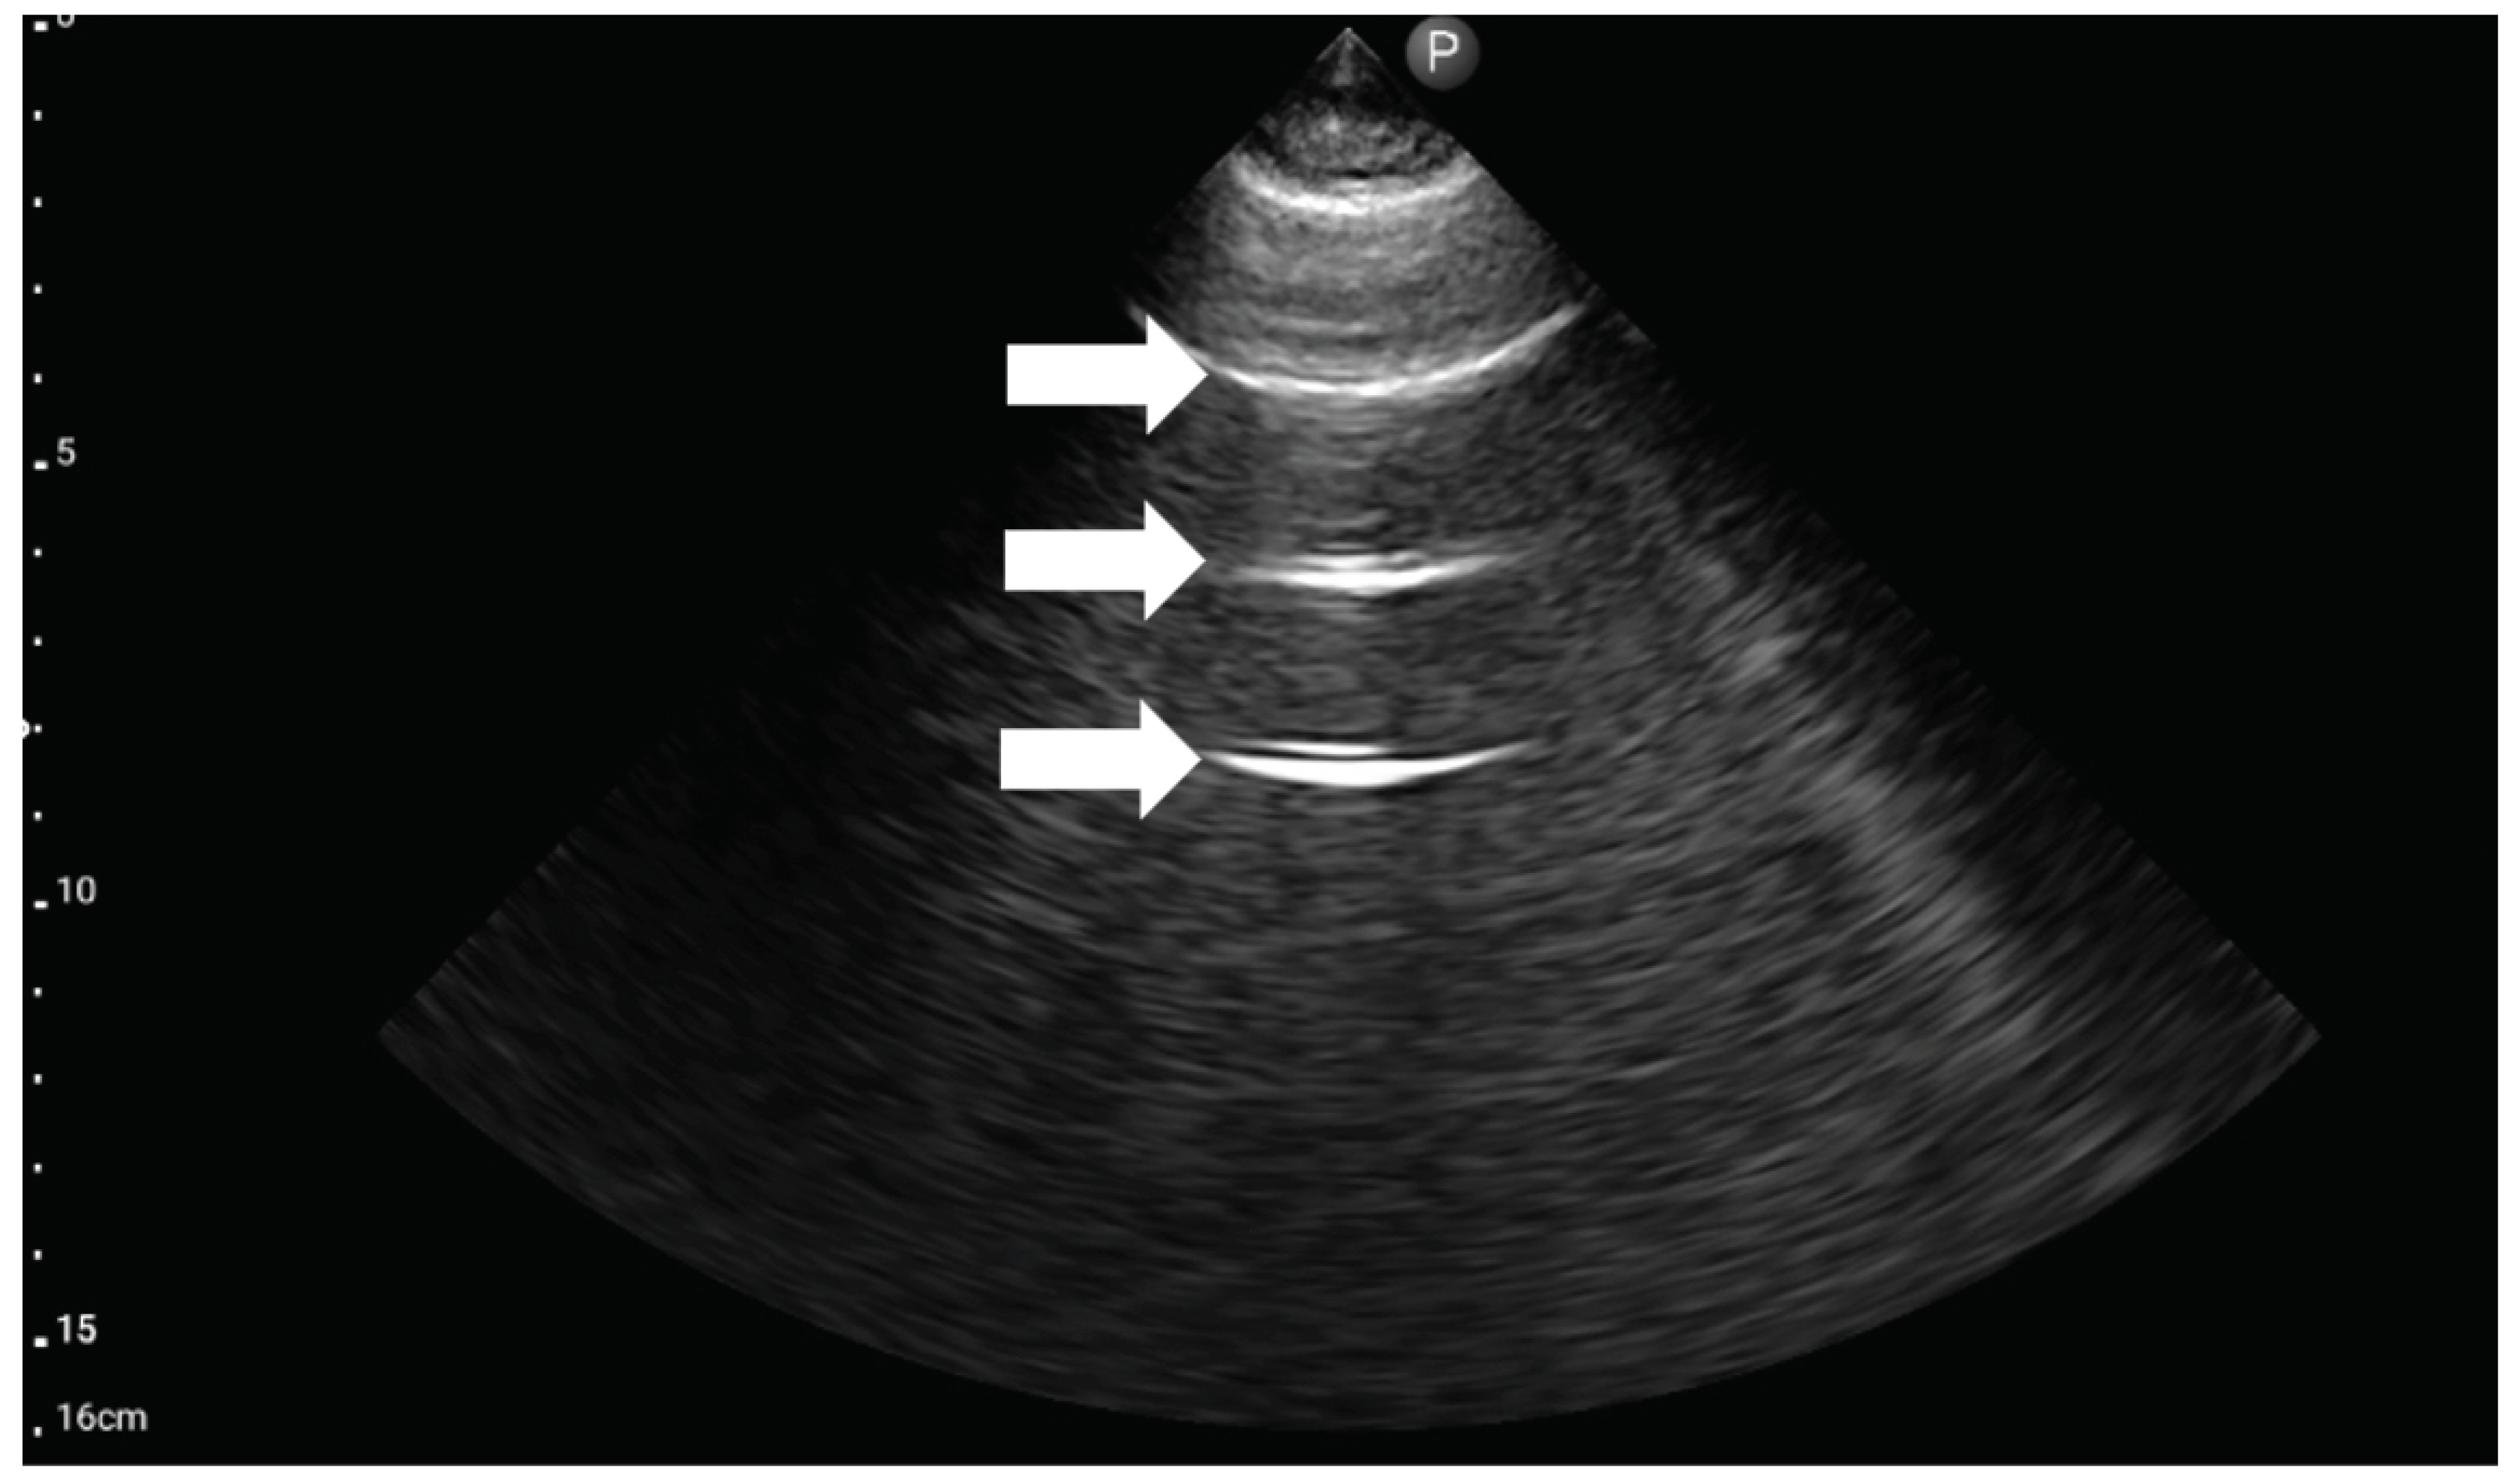

5. BLUE Protocol

To quickly identify and treat the cause of acute respiratory failure, in 2008, Lichtenstein introduced the BLUE (bedside lung ultrasound in emergency) protocol [18]. To date, it is the best known and most accurate of the existing LUS protocols. This study aimed to target diagnostic imaging to identify life-threatening conditions that can lead to acute respiratory failure. Lichtenstein’s task was to develop a protocol by which an ultrasound technician could perform a bedside ultrasound examination in a matter of minutes and implement the correct treatment based on six ultrasound probe positions. The examination is carried out in the chest’s upper (Figure 3), lateral, and posterolateral areas (Figure 4). Within the described six regions on both sides of the chest, the presence of characteristic ultrasound images and signs are assessed, among which are: the A (Figure 5) and B lines (Figure 6), lung sliding sign, lung point (Figure 7), tissue-like sign, and shred sign [18].

Figure 5. Ultrasound symptom “A-lines” (source: author’s material-DK).